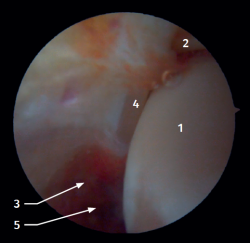

Visión artroscópica anterior

El 20% del LTPA es intraarticular(7). Cuando realizamos un acceso anteromedial del tobillo dirigiendo el artroscopio hacia lateral podemos ver las fibras distales del LTPA con su disposición oblicua y su continuación con el ligamento peroneo-astragalino anterior (Figura 2). Si avanzamos dentro de la articulación tibioastragalina, veremos la articulación tibioperonea distal con el receso sindesmal ocupado de tejido sinovial (Figura 3).

Figura 2. Visión artroscópica anterolateral del tobillo derecho. 1: cúpula astragalina; 2: cara anterior de la tibia; 3: peroné; 4: fibras distales del ligamento tibioperoneo anterior; 5: ligamento peroneo-astragalino anterior.

Figura 3. Visión artroscópica anterolateral de un tobillo derecho al introducirnos en la tibioastragalina. 1: cúpula astragalina; 2: cara articular de la tibia; 3: peroné; 4: articulación tibioperonea distal; 5: fibras distales del ligamento tibioperoneo anterior.